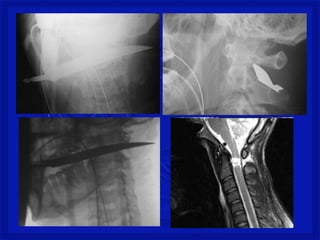

•Perfuração da coluna (arma branca, tiro

ou estilhaço de bomba na coluna)

•Lesão medular completa ou incompleta,

associada ou não a lesão dos nervos

espinhais e/ou tronco dos plexos

nervosos.

•Quadro neurológico é variável.

Mecanismo de Trauma Raqui-

Medular Penetrante

•Perfuração da coluna(arma branca, tiro ou estilhaço de bomba na coluna) •Lesão medular completa ou incompleta, associada ou não a lesão dos nervos espinhais e/ou tronco dos plexos nervosos. •Quadro neurológico é variável. Mecanismo de Trauma Raqui- Medular Penetrante

Gravidade do trauma •DEPENDE SE A MEDULA É ATINGIDA • Lesão medularcervical é a mais comum– 2/3 • C4 a C7 – mais vulnerável a lesão • Torácica - proteção de costelas • Toracolombar– T11, T12 e L1 • Lesão estável ou instável • Difícil de avaliarno pré hospitalar. • Considerartoda lesão instável até se prove o contrario